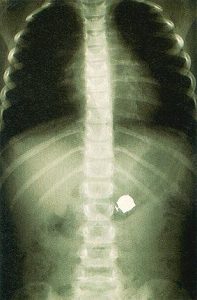

Διάγνωση

Στα πρώτα βήματα της Ιατρικής η διάγνωση βασιζόταν στην ικανότητα του γιατρού να εντοπίσει και να ερμηνεύσει σωστά τις εκ...

Τομομογραφία

Η Υπολογιστική Αξονική Τομομογραφία (CAT , Computerised Axial Tomography) που πρωτοχρησιμοποιήθηκε το 1973 επιτρέπει σήμερα την λεπτομερή απεικόνιση των ...

Ακτινογραφικών τομές

Στην απλή ακτινογραφία οι ακτίνες Χ απορροφούνται σε ποσοστό ανάλογο με την πυκνότητα των ιστών που διαπερνούν. Σε αυτήν την ακ...

Τομογραφία

Η Υπολογιστική Αξονική Τομομογραφία (CAT , Computerised Axial Tomography) που πρωτοχρησιμοποιήθηκε το 1973 στηρίζεται στη λήψη πολλών ακτινογραφικών τομώ...